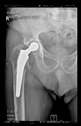

The guiding wire was inserted and controlled with fluoroscopy flashes (Figure 4). The drilling and reaming were carried out in accordance with the recommendations:

Figure 4.

The biocompatible aiming device after insertion of the guiding wire.

The direction of the cup stem was determined by the guide wire. The aiming device was needed to introduce this wire. After removing the aiming device, the next step was the drilling. Since a cannulated drill bit was used, the previously installed wire could guide the process. A self-positioning reaming tool was then used in the drilled channel. In the prepared cavity, the cup was fitted perfectly. Of the two stemmed cups available to us, the McMinn cup (Waldemar Link, Hamburg, Germany) had the simpler geometry and was therefore chosen. The stemmed cup was inserted according to the manufacturer’s recommendation. In the presence of a significant bone defect, a synthetic bone graft may be impacted for substitution.

The radiological examination allowed us to verify the close bone-to-implant contact and the unchanged position of the implant during follow-up.

In all the cases operated with the above-described targeting procedure, the stems of the cups remained between the cortical bone surfaces without perforation of the linea terminalis, as shown by postoperative radiographs. There were no complicated surgical situations. In 16 cases, the wound healings were uneventful, and the hips were able to bear weight again after postoperative rehabilitation.